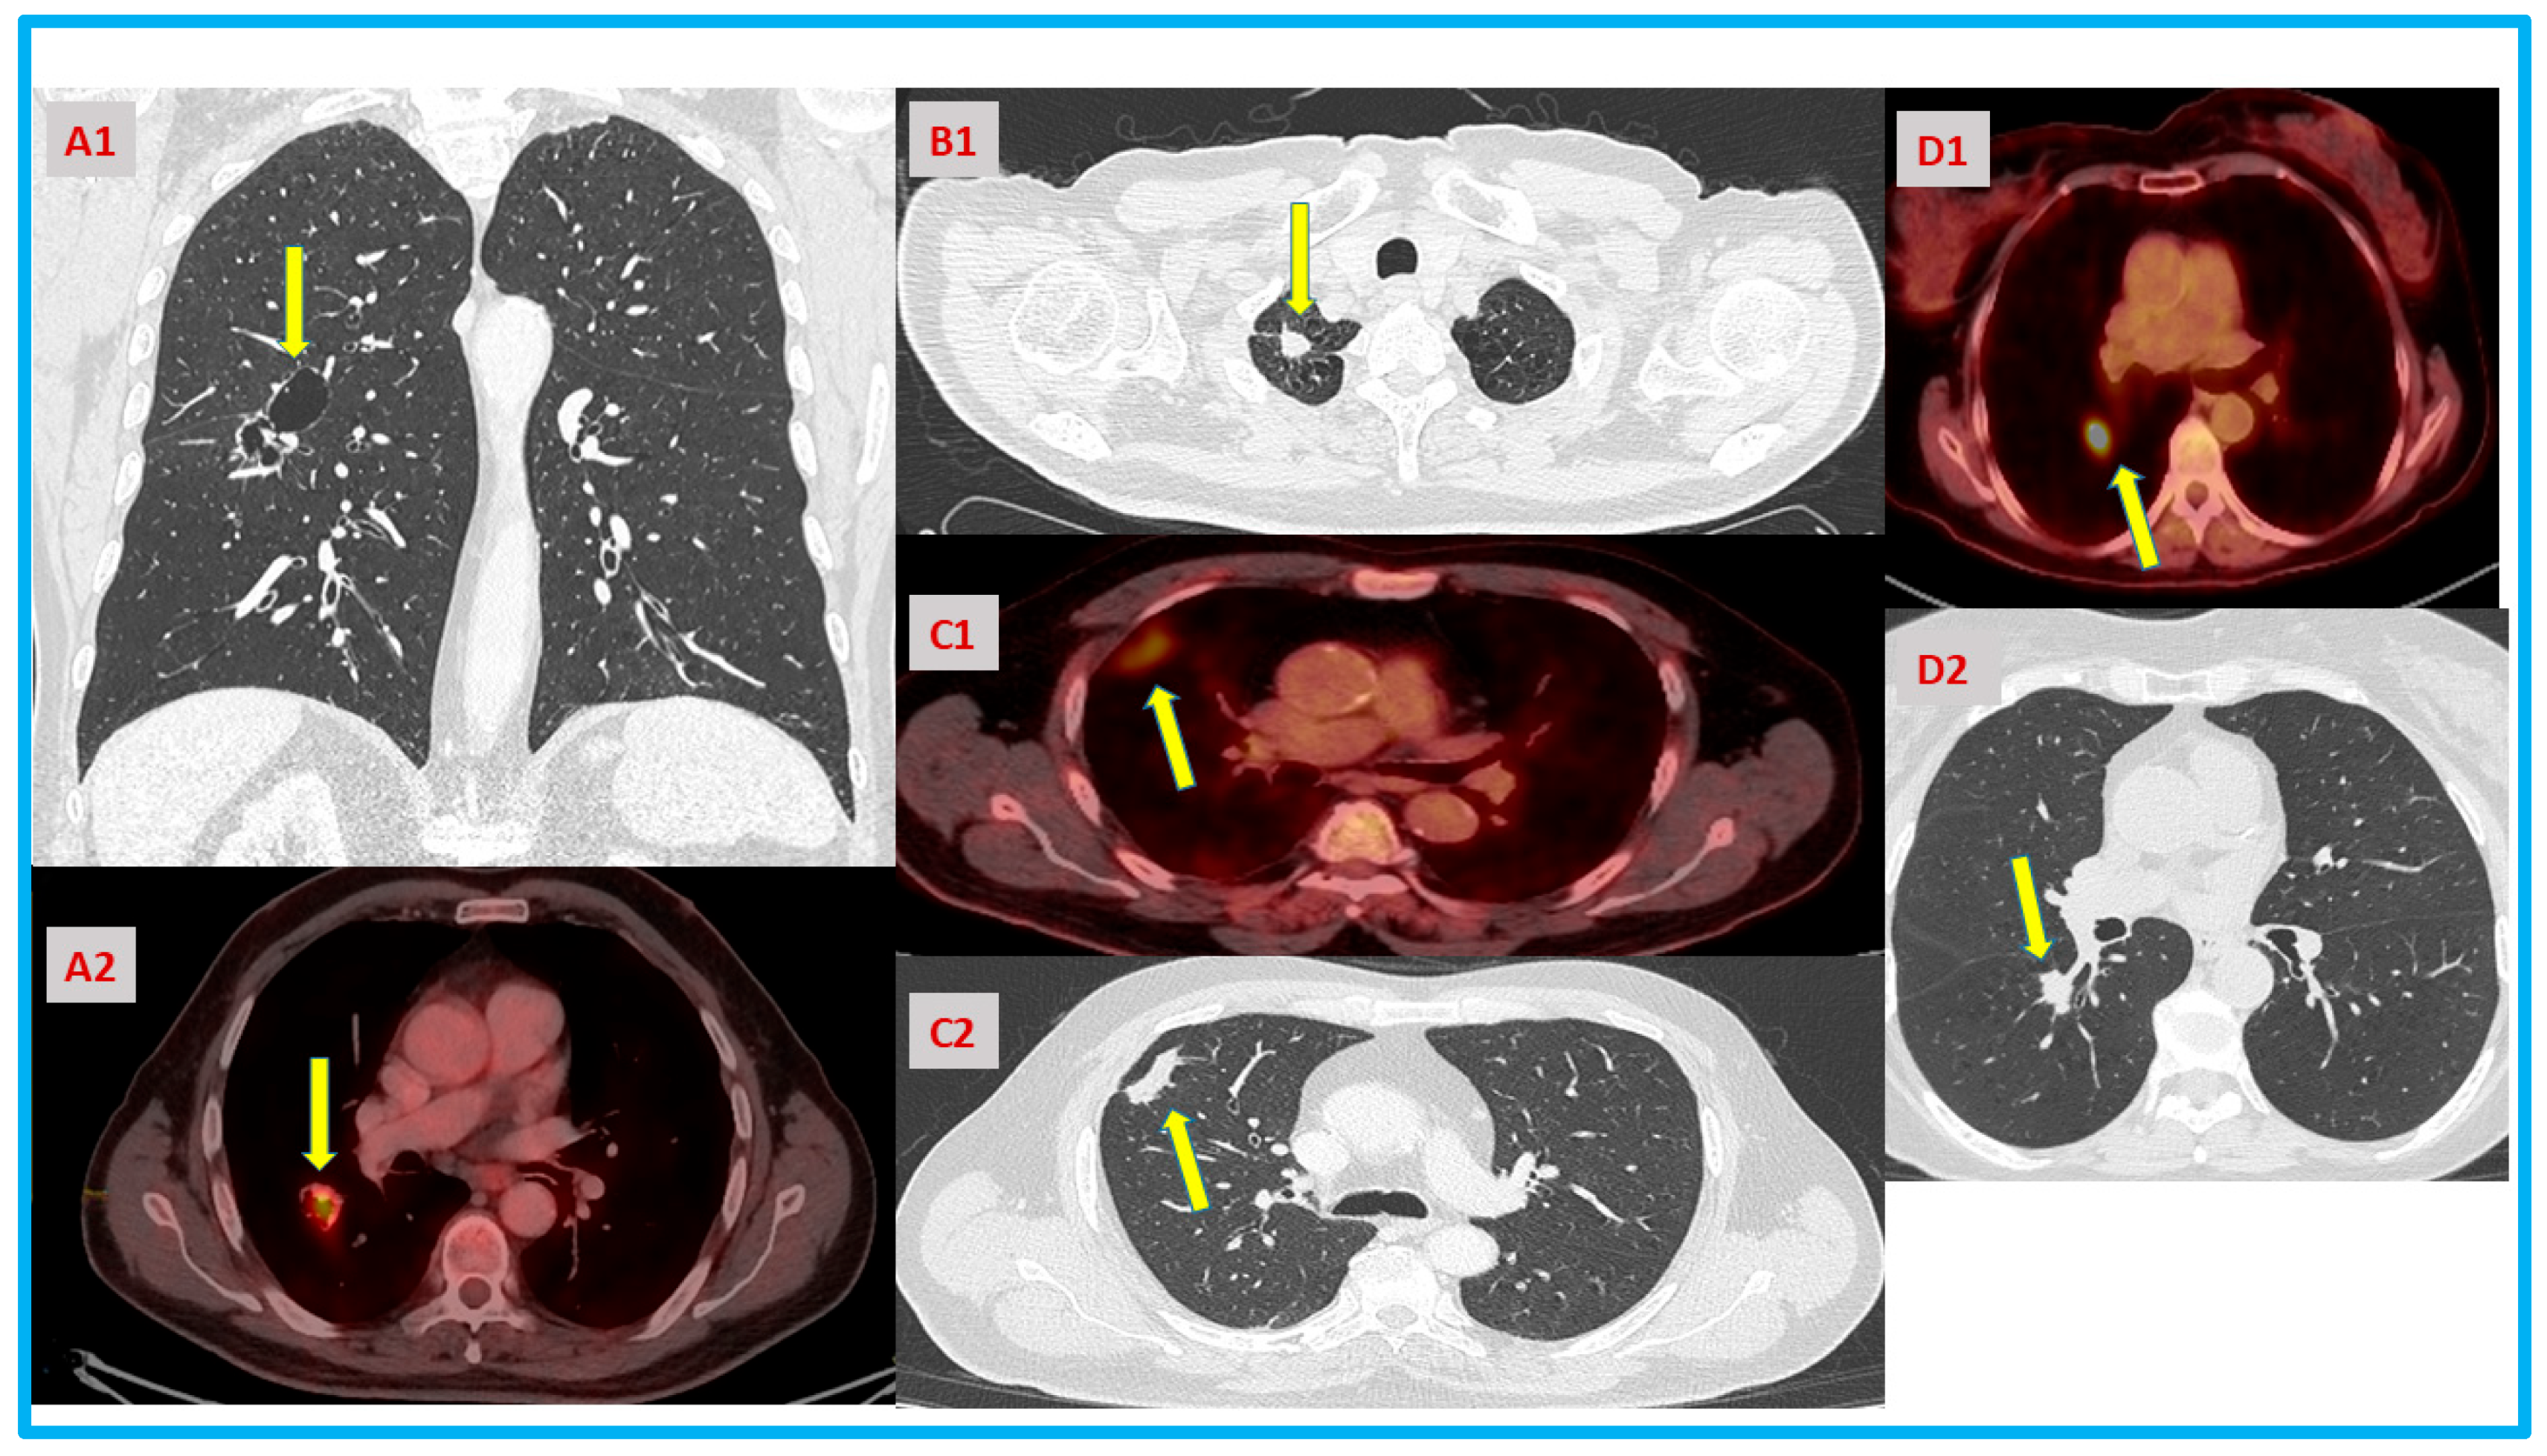

| A | Cavitation with solid component that is not amenable for biopsy would need large resection. Elderly high-risk patient with a limited pulmonary reserve. | Bronchoalveolar lavage. | Validated positive result would help with shared decision making and avoid delay prior to surgery. |

| B | >3 cm lung mass in high-risk patient, not amenable for biopsy. | Patient request to postpone surgery for additional imaging. Later agreed for SBRT. | Validated positive result might help with shared decision making and avoid delay for definitive treatment. |

| C | Persistent consolidation in high-risk patient with negative biopsy. | Needle biopsy, follow-up repeated scans at 3,6 months. Delayed surgery finally. | Validated positive result would prompt earlier surgical intervention. Might avoid stage migration and adjuvant chemotherapy. |

| D | Borderline pulmonary function tests for lobectomy in high-risk patient for both lobectomy and SBRT. | EBUS, navigation bronchoscopy. Offered surgical resection. | Validated positive result would prompt earlier surgical resection. Would help in discussing the risks vs. benefits of surgery vs. SBRT with the patient. |